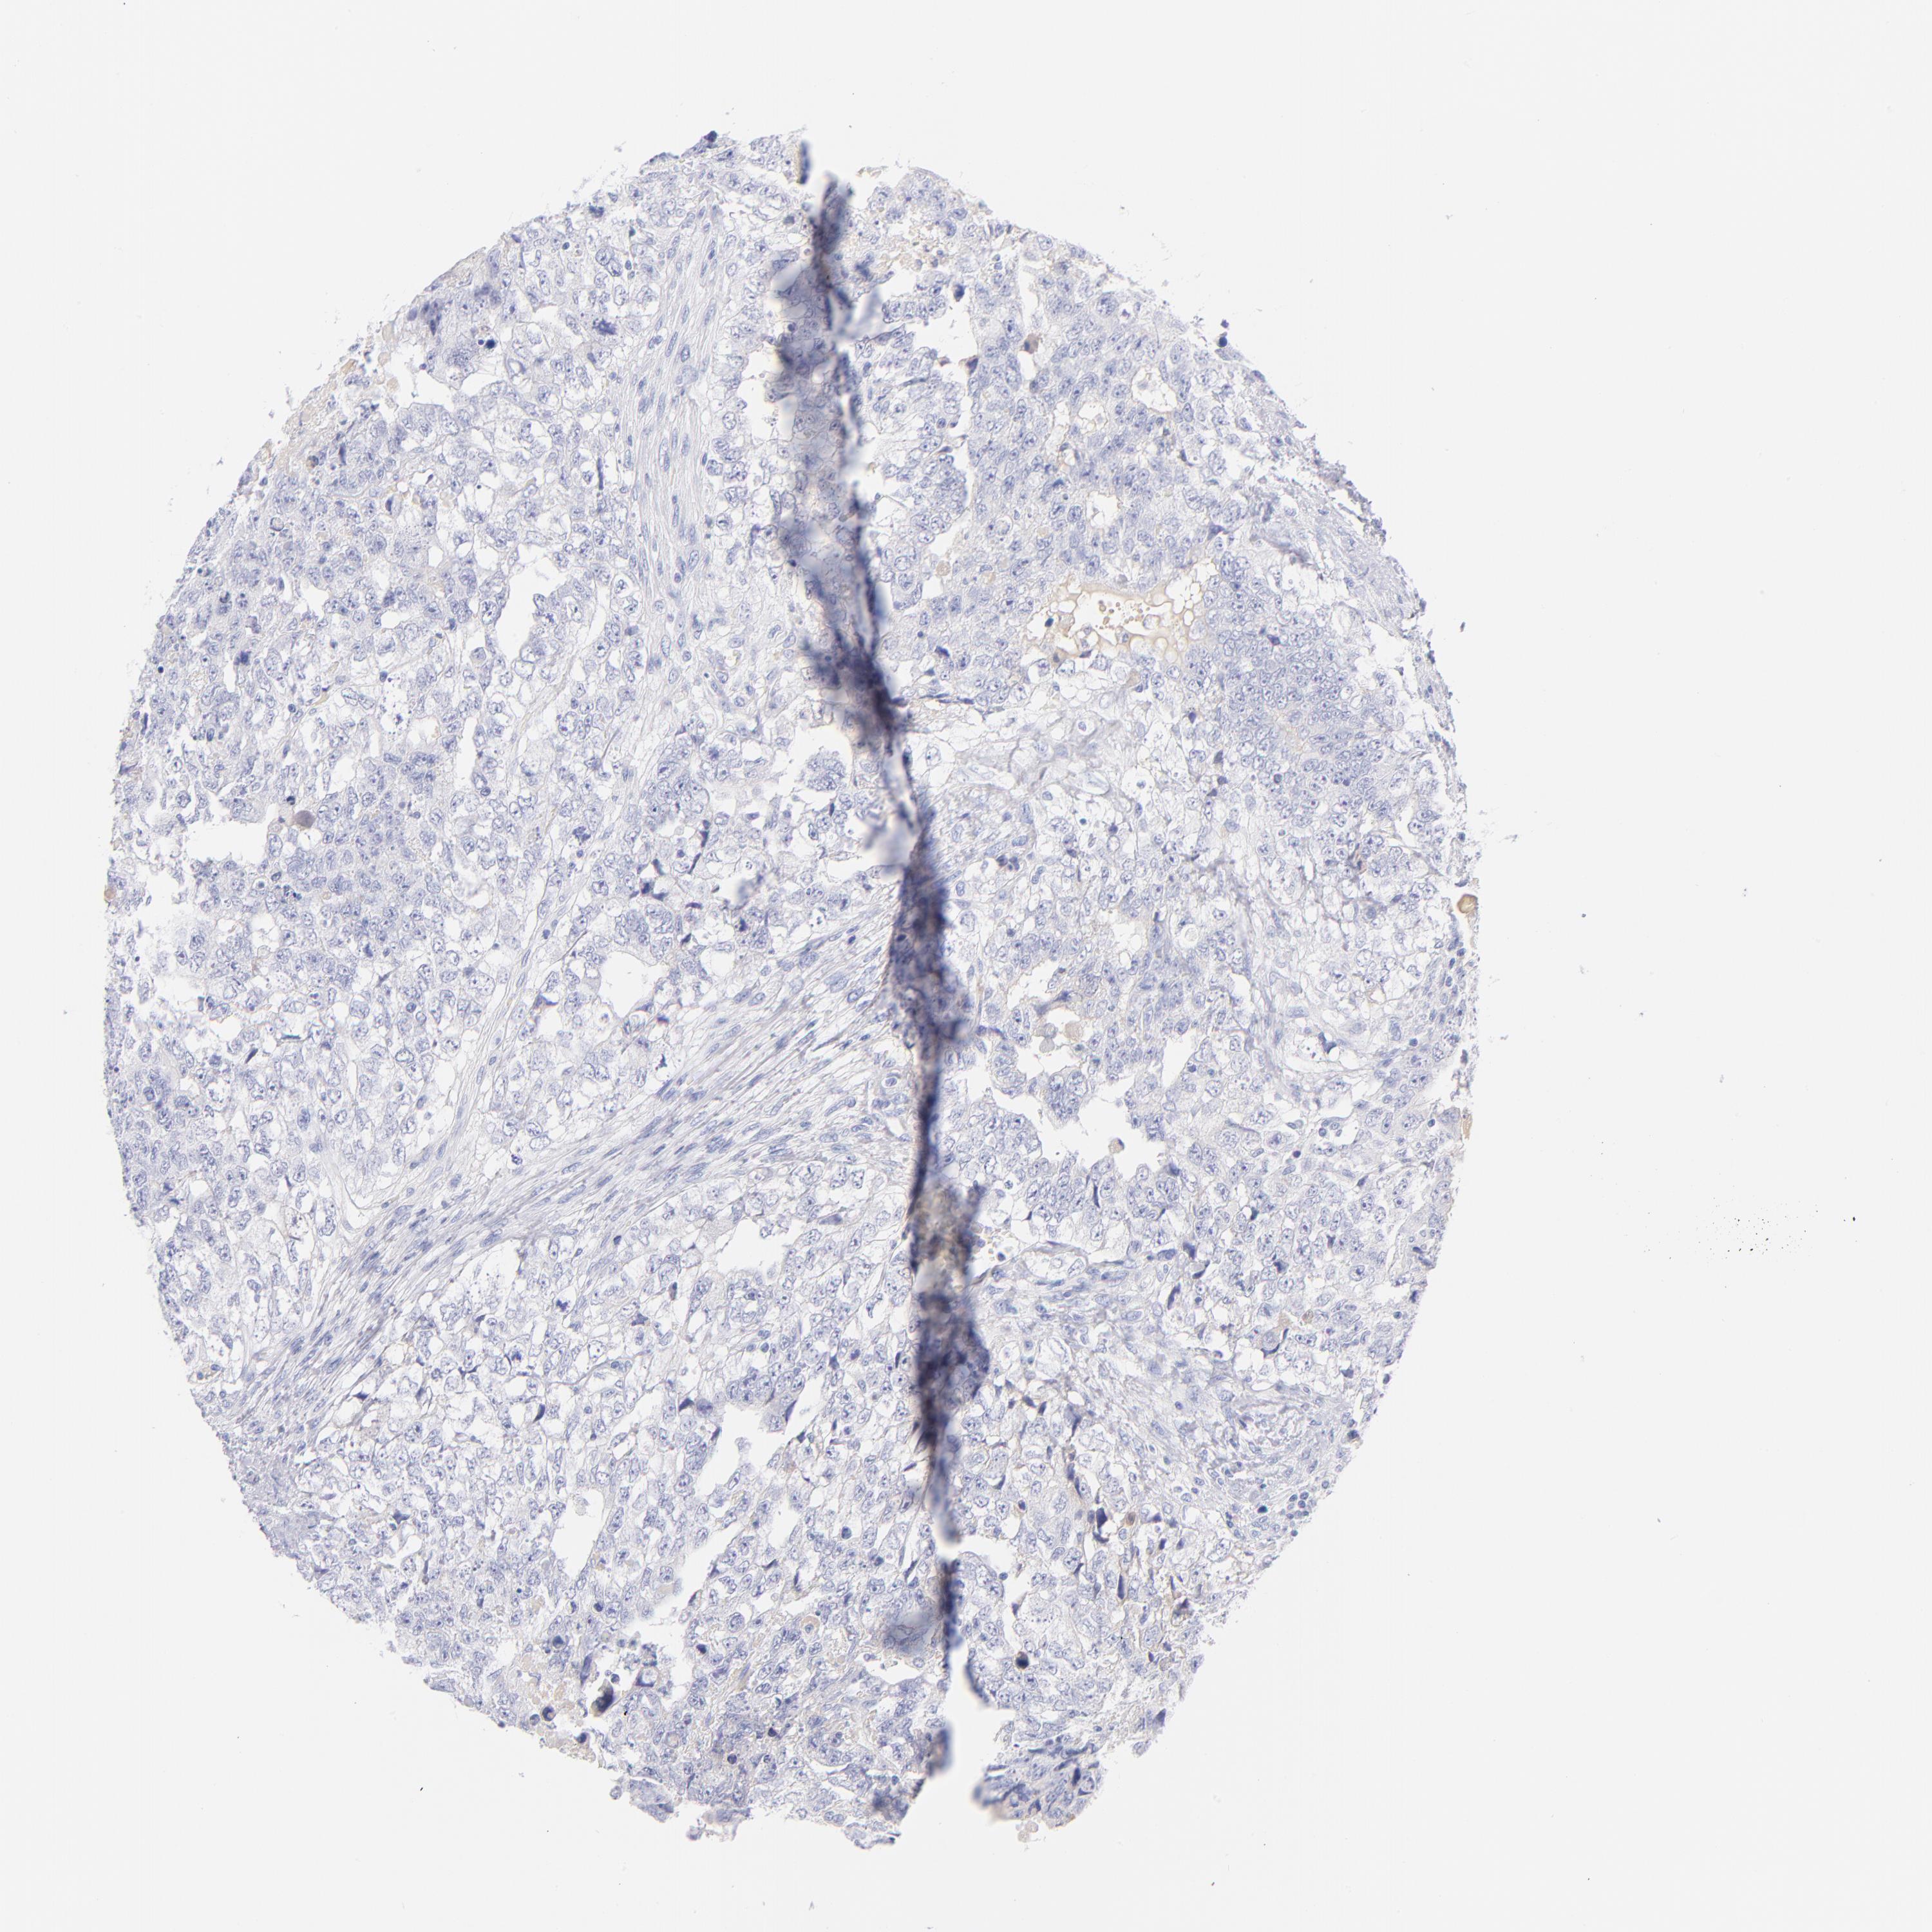

TESTIS CANCER - Protein expressioni

A mouse-over function shows sample information and annotation data. Click on an image to view it in a full screen mode. Samples can be filtered based on level of antibody staining by selecting one or several of the following categories: high, medium, low and not detected. The assay and annotation is described here.

Note that samples used for immunohistochemistry by the Human Protein Atlas do not correspond to samples in the TCGA dataset.

Antibody stainingi

Antibody staining in the annotated cell types in the current human tissue is reported as not detected, low, medium, or high, based on conventional immunohistochemistry profiling in selected tissues. This score is based on the combination of the staining intensity and fraction of stained cells.

Each image is clickable and will lead to virtual microscopy that enables deeper exploration of all samples and also displays staining intensity scores, fraction scores and subcellular localization as well as patient and tissue information for each sample.

Antibody HPA066795

Seminoma, NOS

Carcinoma, Embryonal, NOS